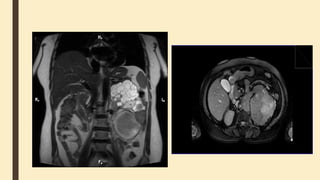

MRI

Renal cortex has slightly higher signal

than medulla on T1-weighted images.

On T2-weighted images, medulla has

slightly higher signal than renal cortex

Simple cyst characteristics are similar

to ultrasound and CT:

■ T1: hypointense (hemorrhagic

debris may mildly increase signal)

■ T1 C+ (Gd): no postcontrast

enhancement

■ T2: strongly hyperintense

(hemorrhagic debris may mildly

decrease signal) and separate

from the collecting system

■ DWI: increased signal, but no

restricted diffusion